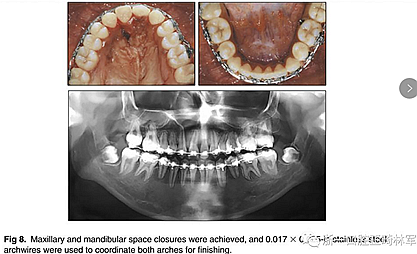

兩年半后,在上下牙弓上均實現(xiàn)了間隙關(guān)閉,并且使用0.017×0.025英寸的不銹鋼弓絲進行咬合精細調(diào)整(圖8)。去除托槽后,上下頜采用舌側(cè)弓進行保持(圖9)。